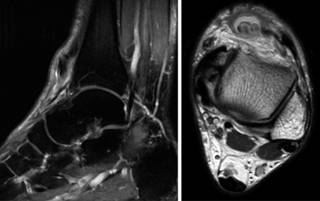

Заболевание суставов: хондроматоз плечевого сустава на снимках МРТ